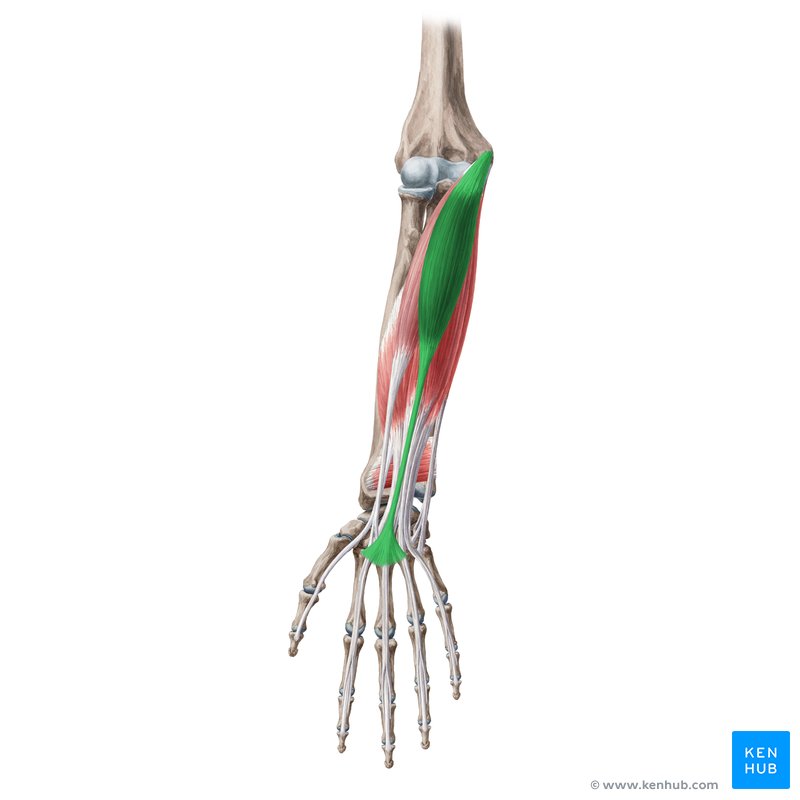

<p>pronate forearm (pr.ter)</p>

pronate forearm (pr.ter)

pronator teres